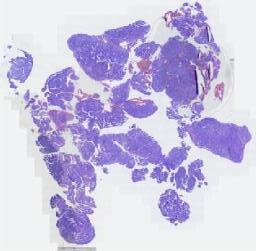

大体所见: 破碎子宫,总体积11.0×7.0x5.0cm,肌壁厚3.0cm,切面局部呈暗红色,内膜灰红色,见一息肉样隆起,大小1.5×0.9×0.4cm。另见灰白组织数块,总体积10.0x7.0x5.0cm,切面灰白灰黄色,部分质软,粘液胶冻状。